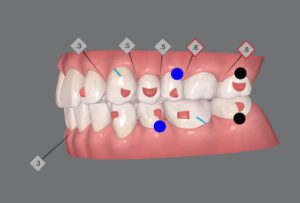

🔶初診時🔶

正面

右

この歯並びは

広島が誇るアラフィフアイドル悪女時代

大倉様

アイドルは

出っ歯じゃ いけんじゃろー

という事でインビザライン開始